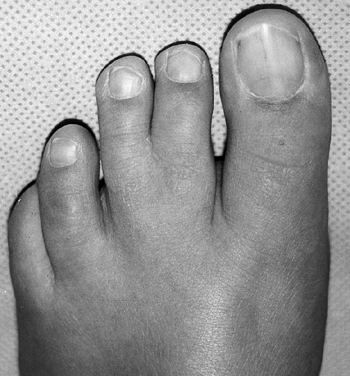

ligaments, allowing only flexion and extension across joints. Each of

the joints has a proximal cylindrical surface with a concave distal

surface. Tendons inserting on the mid and distal phalanx, with

intrinsic muscles acting to flex the metatarsal phalangeal (MP) joint,

function well in the healthy state. This alignment, however, creates an

unstable position of the MP joint in dorsiflexion, once the intrinsic

muscles are unable to flex the proximal phalanx, leading to claw toes.